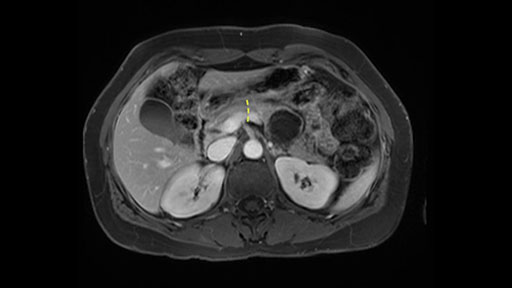

Proximity of lesion to PV-SMV

Key features that I look at the imaging are: first I look at the distance between the cyst and the portal vein SMV confluence. So there are guidelines for this, they call the Yonsei guidelines, to decide to do it laparoscopically or open and basically it says that if it’s a cancer, at least a centimeter away from the celiac trunk or the venous confluence. This is a cyst. So maybe you could stretch that a bit, but you don't want to get into trouble there. So for this cyst if you look at it, it's nicely away from the confluence.

So unfortunately I cannot show you a coronal view but you can see it easily on this scan, going down first you see the celiac trunk and you see here, quite a nice distance between the celiac trunk and the beginning of the mucinous cyst. And if you go up here and follow down the portal vein confluence you also see a nice distance there.

So what I would normally do in these patients, I would look at the abutment of any other organs, one, which is here, potentially the adrenal gland and two the small bowel. And two, look at the distance from the vessels which I would normally do in a coronal view. So you can easily measure the distance and third I look at the insertion of the inferior mesenteric vein. Now we can probably also see that on here. Although it's better on a CT scan and it's better on a coronal view, you want to know where the inferior mesenteric vein comes into either the splenic or the SMV, because that is typically a very important slow down moment when you mobilize the lower portion of the pancreas knowing where the inferior mesenteric vein comes in either the splenic vein or the SMV. So those are I think the three most important points for the CT scan.